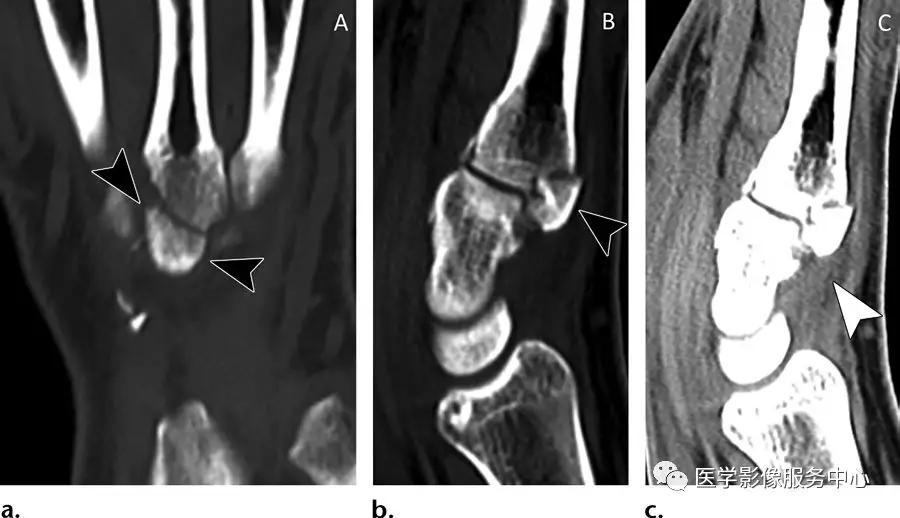

桡侧腕短伸肌的撕脱骨折:

(左图,中图)第三掌骨基底部的略示移位骨片影(黑色箭头)。(右图)桡侧腕短伸肌腱的远端(白色箭头)插入第三掌骨基底部的骨片。